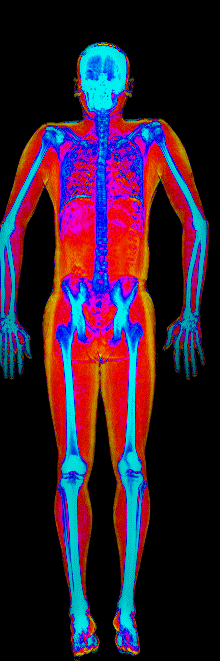

A DEXA scan passes two low-dose X-ray beams through your entire body, head to toe. Different tissues absorb different amounts of energy: bone absorbs the most, muscle and lean tissue less, and fat the least. The scanner reads how much energy made it through every pixel and assigns each one to a tissue type.

The colorful image at the top of every BodyStats DEXA report is literally that map. Bone shows up in cyan and white. Lean tissue is red. Fat is yellow and orange. Your body-fat percentage isn’t an inference — it’s a count of how much of that image is yellow and orange, broken out region by region: left arm vs right, left leg vs right, trunk, android (belly), gynoid (hips). And visceral fat — the dangerous abdominal fat that bioimpedance can’t see at all — comes back as its own number in cm².

This page features real, anonymized DEXA scan images from BodyStats clients, organized by gender and body fat percentage in 5% increments. DEXA (Dual-Energy X-ray Absorptiometry) is the clinical gold standard for measuring body composition — far more accurate than scales, calipers, or visual estimates.

Each colorized scan shows the distribution of fat tissue (shown in warmer colors) and lean tissue (cooler colors) throughout the body. Compare your own DEXA scan to others in your range, or see what different body fat levels actually look like on a scan.

Male DEXA Scans by Body Fat %

20 to 25% body fat